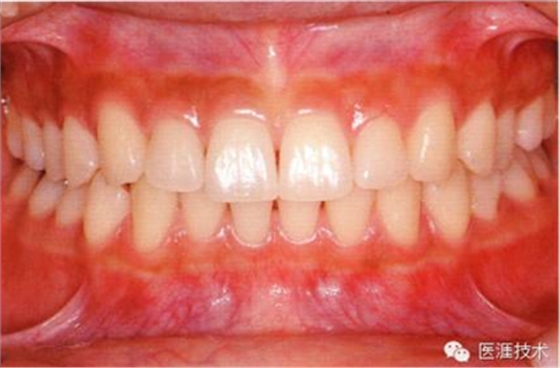

28歲女性的健康口腔內(nèi)部

圖為28歲女性,無特殊全身疾病,不抽煙。10年前來院就診保養(yǎng)3年,期間中斷過,現(xiàn)又開始。齲壞風險高,當初初診時已有好幾顆牙的鄰面有填充物,再填充了3牙的鄰面齲,現(xiàn)牙周組織健康。